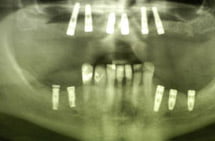

Uzupełnienia bezzębia żuchwy implantami wykonanymi w systemie Ankylos.

Pacjent z brakami częściowymi górnymi i dolnymi. Usunięto zęby ze wskazań chirurgicznych, pozostawiając górną szczękę bezzębną, a w żuchwie braki skrzydłowe. Wprowadzono 6 implantów w szczęce i 5 w żuchwie. Po okresie osteointegracji odbudowano szczękę i żuchwę uzupełnieniami stałymi porcelanowymi na cyrkonie i łącznikach tytanowych.